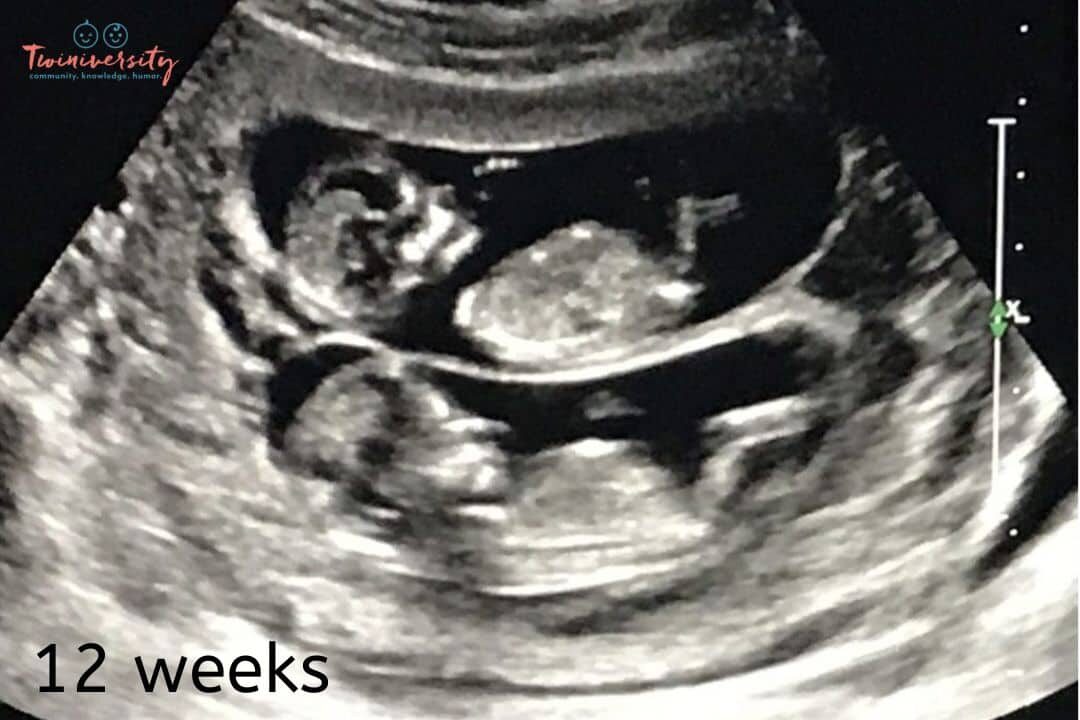

“Did anyone have an ultrasound at 12 weeks and they missed one of your twins?” t

Found out about the twins at the 12-week ultrasound, which was our 3rd ultrasound! Only one baby in all the previous ones.

8 weeks, one baby and 12 weeks two babies

Again, it’s rare but possible to experience a “hidden twin” during your pregnancy. Mostly, the imaging available nowadays will pick up a second baby pretty early on. But a twin can be overlooked, especially if your provider isn’t looking for a twin at first glance.

Twins can typically be detected on ultrasound during the first trimester, usually around 6 to 8 weeks of gestation. In some cases, healthcare providers may be able to identify the presence of twins even earlier, especially with advanced ultrasound technology. The ability to visualize twins on an ultrasound depends on factors such as the clarity of the image, the position of the embryos, and the experience of the ultrasound technician.